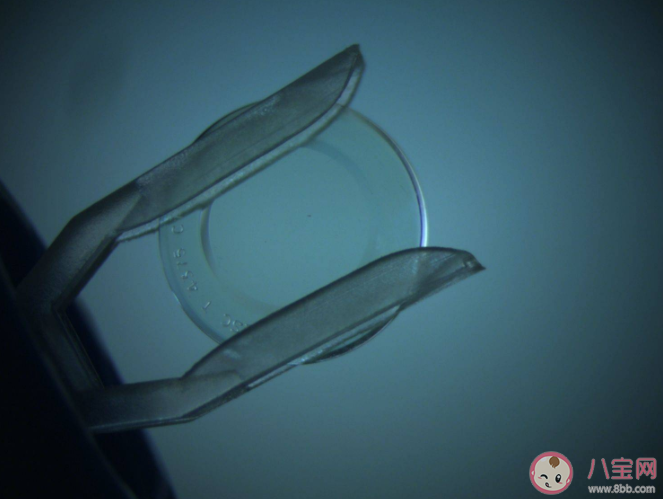

流言:眼球软,OK镜硬,会磨损眼球导致角膜变薄,不能常戴。

真相:OK镜又叫角膜塑形镜,是一种非手术的屈光矫正方法。OK镜与眼球之间基本不会发生相对运动,材料也很安全,正确使用不会磨损角膜。需要注意的是,不是每个近视者都适用OK镜,应由专业机构医师判断、验配。角膜塑形镜作用是可逆的,如果停戴两周,角膜形态将基本恢复。此外,OK镜的清洁和护理一定要规范,以免镜片污染引发角膜炎。